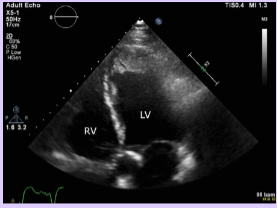

LV thrombus

Most common form of intracardiac thrombus due to impaired LV function.

Rarely occur in patients with preserved LV function.

Commonly found in the apex.

High risk for thromboembolic events, particularly stroke.

<p>Most common form of intracardiac thrombus due to impaired LV function.</p><p>Rarely occur in patients with preserved LV function.</p><p>Commonly found in the apex.</p><p>High risk for thromboembolic events, particularly stroke.</p>